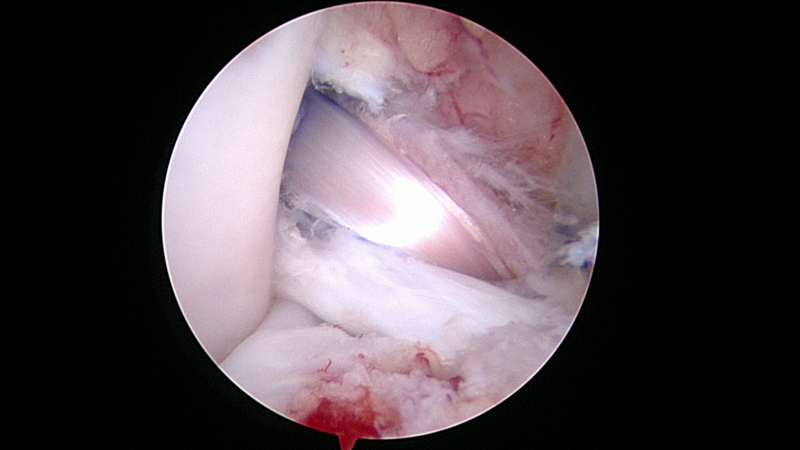

Arthroscopic view of ACL reconstruction technique in a dog

Drs. Jimi Cook, Pat Smith, Jim Stannard, Ferris Pfeiffer, Cristi Cook, and Kei Kuroki recently received a grant from Arthrex to study the latest technique for ACL surgery—double bundle reconstruction using suspension fixation.  The research team developed a novel all-arthroscopic model in dogs to effectively test this technique for human application, while helping our four-legged patients at the same time.  This month (April 2013) the first-ever procedures were successfully performed in dogs, and within this calendar year we will know if this technique will provide a better solution for patients around the world.